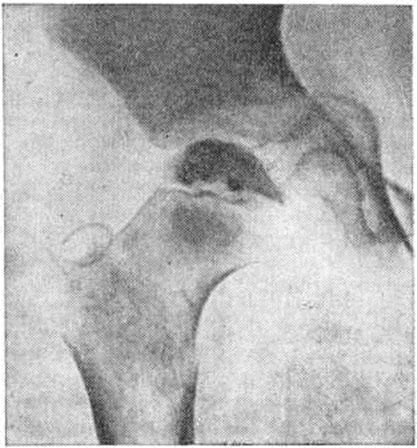

Вторая стадия — стадия импрессионного перелома: головка бедренной кости уплощена, уплотнена, лишена структурного рисунка, имеет неровные извилистые контуры (рисунок 1).

Рис. 1.

Прямая рентгенограмма правого тазобедренного сустава ребёнка 8 лет с болезнью Пертеса (вторая стадия заболевания): головка бедренной кости несколько уплощена, уплотнена, лишена структурного рисунка, имеет неровные извилистые контуры.